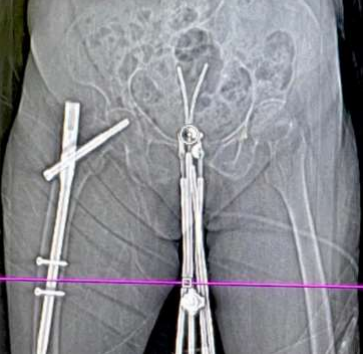

She received the planned EBRT of 50Gy/25# (23# of pelvic irradiation by four field box technique f/b two fractions parametrial boost) in April-May/2022 (last fraction of EBRT on 31/5/22) at a peripheral cancer centre with no brachytherapy facilities. She was referred to our Centre for brachytherapy to complete the treatment. Four fractions of intracavitary brachytherapy two days a week apart, two fractions each day, with a minimum of 6-8 hours between each fraction on each day of brachy delivery (on the 29th of June and the 6th of July 2022). The patient insisted on limited visits because of the long distance from her home. The dose per fraction was 6Gy, and a Fletcher suit with 2.0 cm ovoids was the applicator used for the ICBT. A free tandem(non-dominant) was used in the contralateral cornua, and the dose was optimised to maintain the target and organ at risk constraints. Source loading was done only in the free tandem's distal half to optimise the junctional region's dose.  The free tandem was swapped between the cornua on the two days. Planning was done using Brachyvision Version 8.6, and treatment delivery was done with the Varisource machine (Figures 3, 4 & 5). The EQD2 to the target and OARs (in Gray) were as follows: Tumour (HRCTV)- 80, 2cc of bladder, rectum and sigmoid were 82.8, 74.2 & 78.1 respectively (ABS X-cel sheet was used for EQD2 calculation). At 15 months’ follow-up, the patient is disease-free.

Figure 3: Topogram at the time of brachytherapy simulation